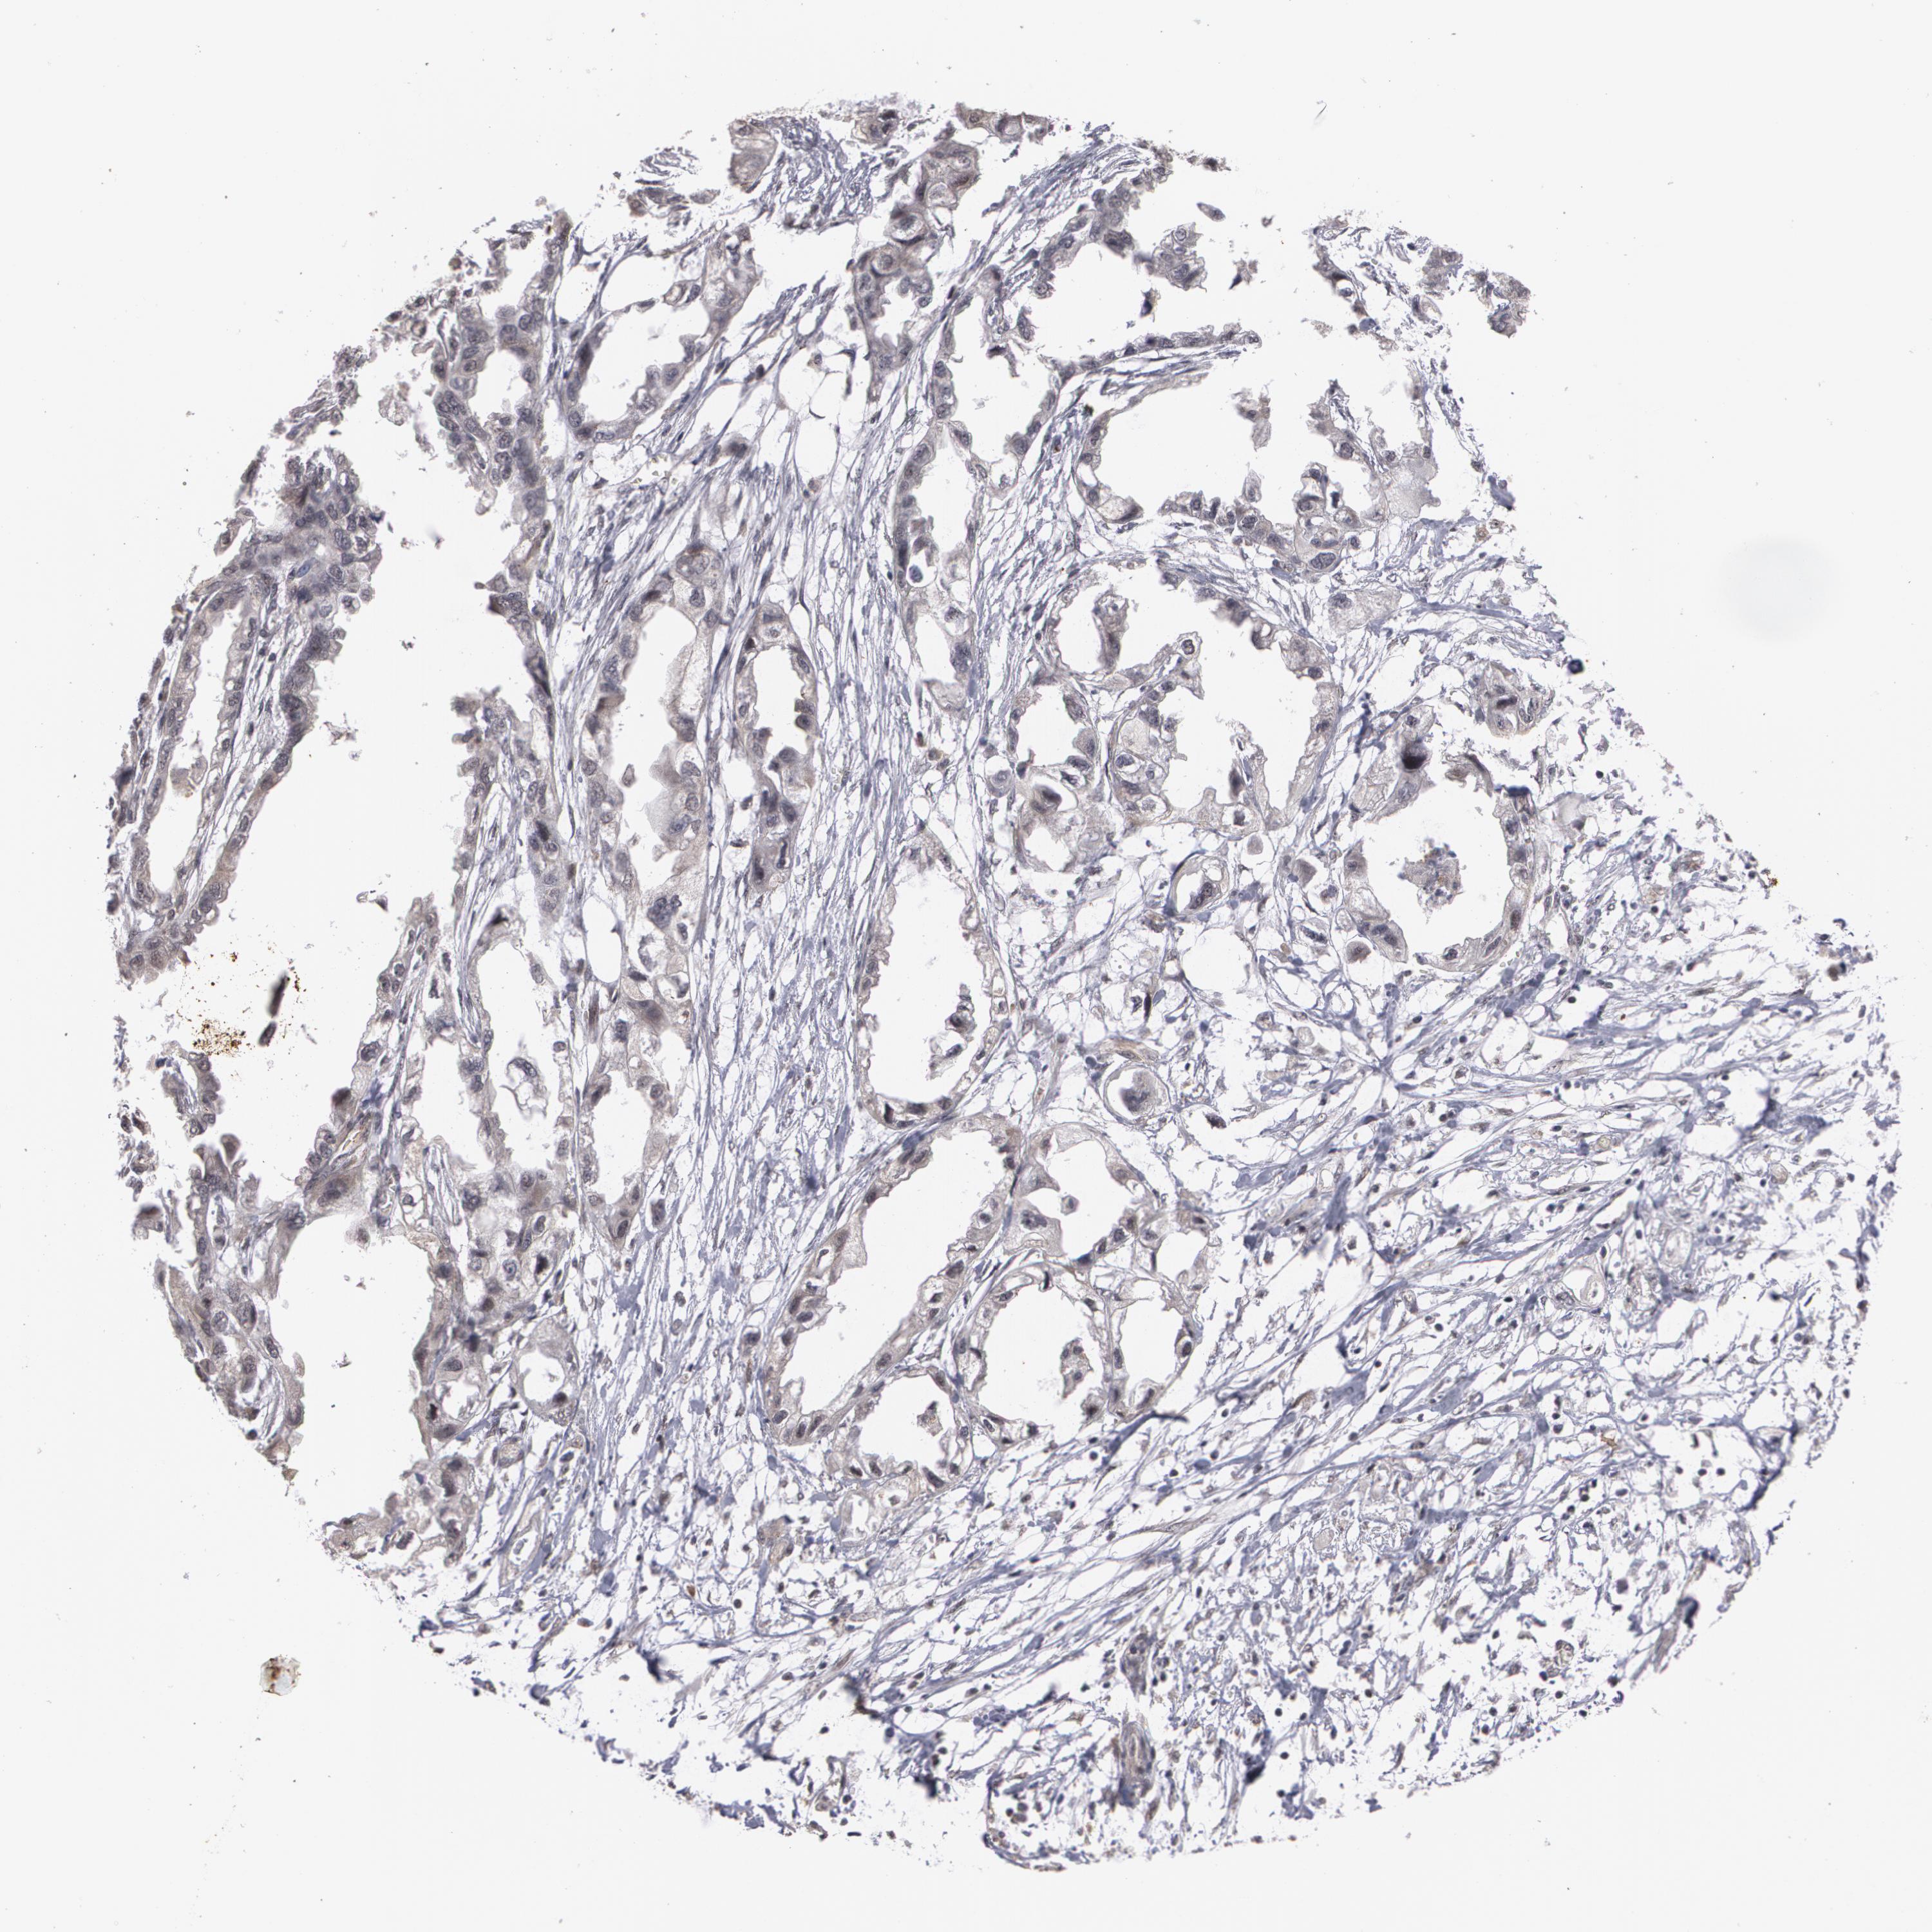

ENDOMETRIAL CANCER - Protein expressioni

A mouse-over function shows sample information and annotation data. Click on an image to view it in a full screen mode. Samples can be filtered based on level of antibody staining by selecting one or several of the following categories: high, medium, low and not detected. The assay and annotation is described here.

Note that samples used for immunohistochemistry by the Human Protein Atlas do not correspond to samples in the TCGA dataset.

Antibody stainingi

Antibody staining in the annotated cell types in the current human tissue is reported as not detected, low, medium, or high, based on conventional immunohistochemistry profiling in selected tissues. This score is based on the combination of the staining intensity and fraction of stained cells.

Each image is clickable and will lead to virtual microscopy that enables deeper exploration of all samples and also displays staining intensity scores, fraction scores and subcellular localization as well as patient and tissue information for each sample.

Antibody HPA001665

Staining

High

Medium

Low

Not detected

Intensity

Strong

Moderate

Weak

Negative

Quantity

>75%

75%-25%

<25%

None

Location

Nuclear

Cytoplasmic/membranous

Cytoplasmic/membranous,nuclear

Adenocarcinoma, NOS

Neoplasm, malignant, NOS